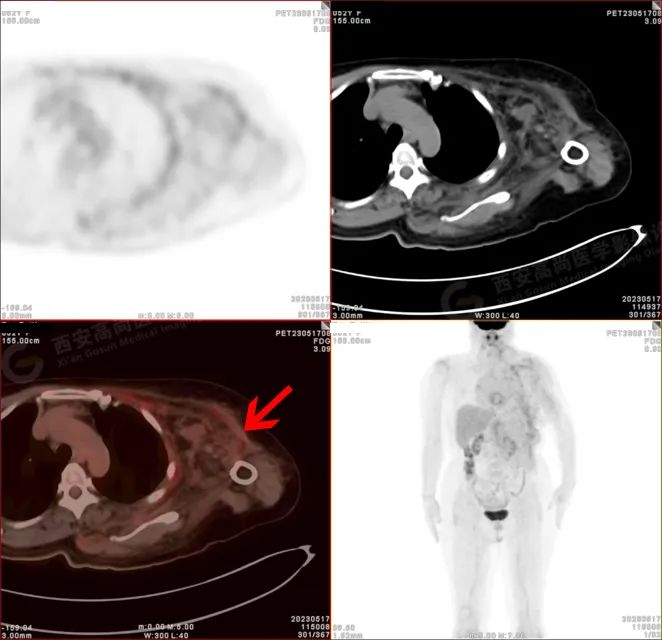

PET/CT 影像图

检查所见

左侧上臂、颈 4-腰 4 椎体水平左侧颈、左侧肩部、左侧腋窝、左侧胸部(含左侧乳腺)、左侧腹部、左侧背部广泛区域皮下及肌肉区可见疏松、肿胀混杂密度软组织病变,边界模糊不清,相邻骨质结构完整,上述病变呈不均匀放射性摄取轻度异常增高,SUV 最大值介于 1.2-2.4。上述改变,符合韧带样纤维瘤病。